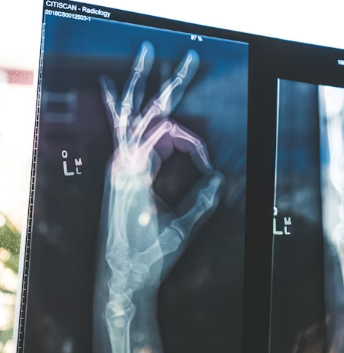

류마티스 관절염은 초기에는 증상이 서서히 나타나거나 다른 관절 질환으로 오인하기 쉽습니다. 손가락, 손목, 발가락 등 작은 관절에서 시작되는 경우가 많으며, 양쪽에 대칭적으로 나타나는 경향이 있습니다. 다음과 같은 증상들이 반복되거나 지속된다면 류마티스 관절염을 의심해 볼 수 있습니다.

관절이 붓고(부종), 열감이 느껴지며, 누르거나 움직일 때 통증이 나타납니다. 주로 손가락 중간 마디, 손목, 발가락 관절 등 여러 관절에 동시에 나타나고 양쪽에 대칭적으로 발생하는 경향이 있습니다.

통증은 휴식 시에도 나타날 수 있으며, 염증이 심할수록 통증과 부종이 심해집니다. 관절 주변 피부가 붉게 변하기도 합니다.